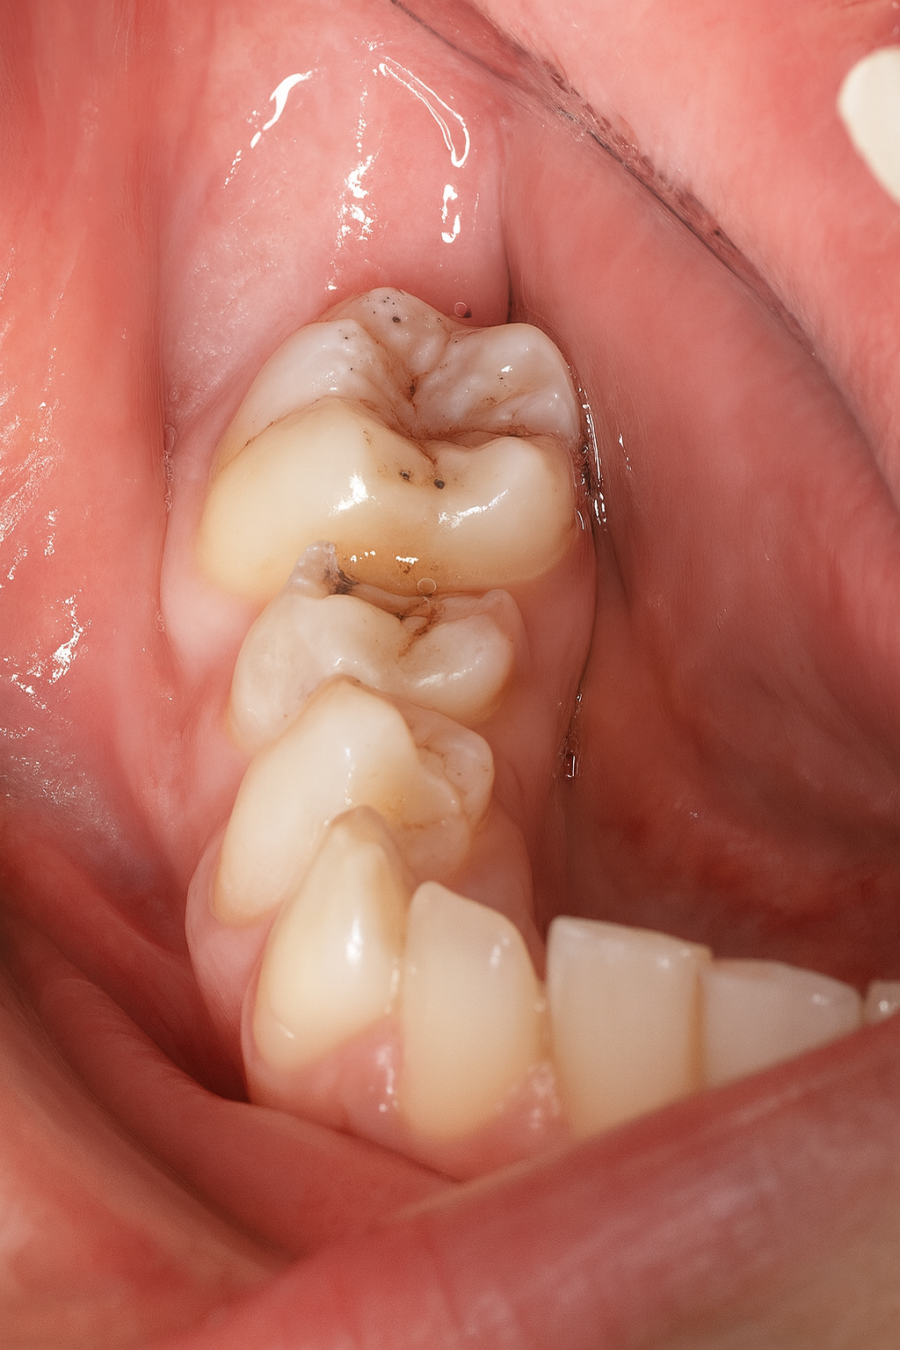

Métodos: Se presenta el caso clínico de un paciente varón de 18 años en el que, tras la realización de una CBCT de la arcada mandibular, se observó la retención de los segundos molares mandibulares permanentes junto con los terceros molares mandibulares.

Clínicamente la impactación de los 2M puede dar lugar a diversas complicaciones locales, entre las que se incluyen la aparición de lesiones quísticas, procesos infecciosos como la pericoronaritis o los abscesos, así como la sobreerupción de dientes antagonistas. Además, esta condición puede favorecer la aparición de patologías en los dientes adyacentes, tales como reabsorción radicular, caries, alteraciones periodontales, repercusiones estéticas y funcionales, incluyendo dificultades masticatorias7.